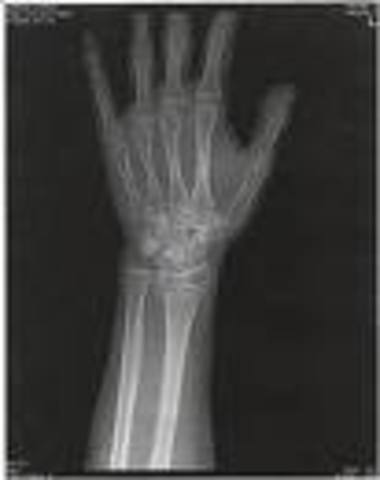

The accident

The winter of 2003 was when i began to snowboard. I had just finished my lesson with my instuctor and I wanted to go on a bigger hill. So me and my father went to a new hill, while going down the hill i fell and broke my wrist in two places! This changed me because now I am more carefull in anything I do and im a little less reckless.